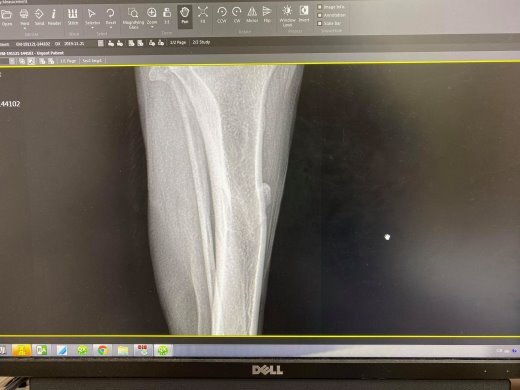

- 編號: 9414

主題: 英文的黃金右腳無法點地、月亮的香港腳 申請者姓名: 臺北市支持流浪貓絕育計劃協會 花色: 申請日期: 2019-12-06 19:29:30 申請者部落格: 申請者臉書網址: 所在縣市/合作醫院: 台北市/其他院所醫助專案(醫院請先MAIL溝通) 治療費用: 10785元 需求人數: 43人 已結案 (2024-05-31 18:22:53) 報名人員: Yen-Yuan Wang(已付款)、philtery x7(已付款)、Kristy Lee x2(已付款)、Elisha Wang x10(已付款)、Tracy Kao(已付款)、Coffeemilk x5(已付款)、ShenJang Fann x8(已付款)、Sze Chi Huang x9(已付款)、 候補人員: 動物病情說明: 11/21沐恩-英文因右後腳無法點地就診

照X光發現骨頭增生

醫師懷疑有異常

等過2週後再照X光比對

12/4麗園-英文照X光